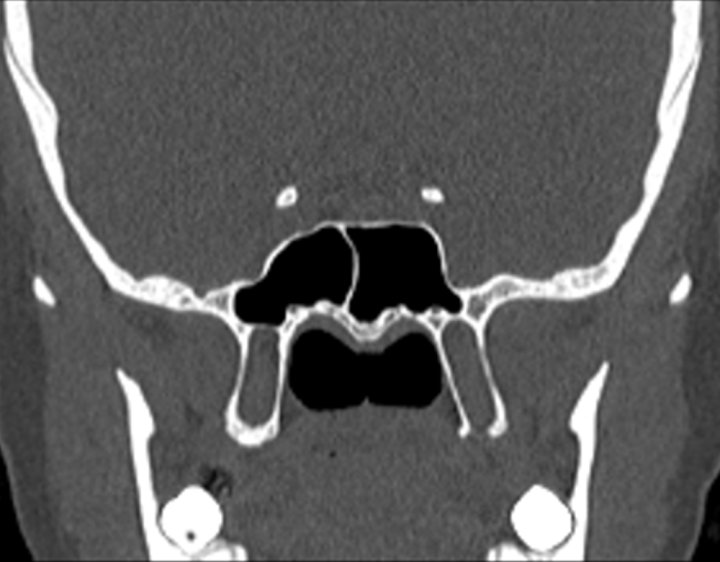

Click any image for labels.